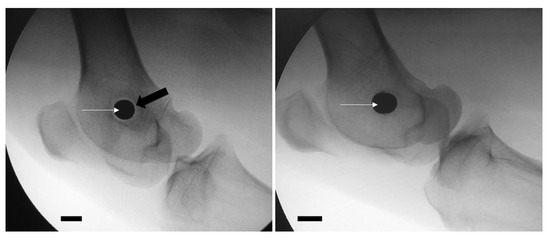

2.3.5. X-rays

3.2.4. X-rays